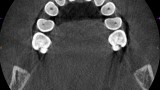

Resorpcja zęba to proces powstania ubytku twardych struktur zęba wywołanego przez osteoklasty bez kontaktu ze środowiskiem jamy ustnej, między innymi na skutek ucisku wywieranego przez ząb zatrzymany. Dla lekarza ortodonty jest istotne ustalenie, czy zęby zatrzymane lub twory nadliczbowe powodują resorpcję zębów stojących w łuku w celu wczesnej eliminacji przyczyny resorpcji. Celem pracy jest przedstawienie opisu przypadku zastosowania tomografii stożkowej w diagnostyce nieprawidłowo położonych zawiązków zębów przedtrzonowych drugich górnych. Stwierdzono, że tomografia stożkowa jest skuteczną metodą oceny wczesnej resorpcji zewnętrznej korzeni zębów.

Tooth resorption is the process of appearing of a defect of hard tissues of teeth caused by osteoclasts not having contact with oral cavity environment, eg. due to mechanical pressure exerted by an impacted tooth. It is essential for an orthodontist whether impacted teeth or supplementary teeth cause resorption of erupted teeth in order to early eliminate the causative factor of the resorption. The aim of the paper is to describe a case report of cone-beam computed tomography (CBCT) in diagnostics of incorrectly located germs of upper second premolars. It was found that CBCT was an efficient method of imaging of early external root resorption.